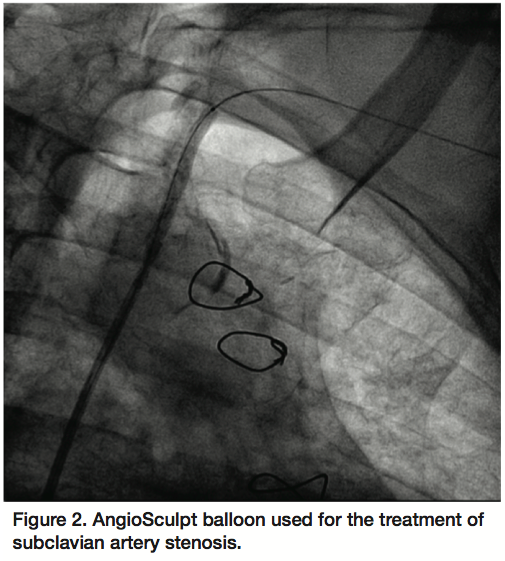

A 6 Fr, 65 cm sheath (Terumo Corporation, Tokyo, Japan) was used to engage the origin of the left subclavian artery via the right femoral artery. Unfractionated heparin anticoagulation was used during the procedure. A V18 Control Wire guidewire (Boston Scientific) crossed the severely calcified, eccentric lesion in the subclavian artery. An AngioSculpt 4 x 40 mm scoring balloon catheter (AngioScore) was used for predilatation given the calcific burden of the lesion (12 atm, 40 seconds) (Figure 2). The V18 guidewire was then exchanged for a Supra Core 0.035 guidewire (Abbott Vascular) over which a subsequent predilatation was performed with a 5 x 40 mm FoxCross balloon (Abbott) (9 atm, 30 seconds). An Express LD 8 x 27 mm balloon-expandable stent (Boston Scientific) was deployed (10 atm, 20 seconds) (Figure 3) and postdilatation was performed with a 9 x 20 mm Admiral Xtreme balloon (Invatec, Medtronic, 9 atm, 20 seconds). An excellent angiographic result was achieved (Figure 4) with minimal residual left subclavian stenosis and no gradient across the lesion. In addition, at the end of the procedure there was angiographic evidence of antegrade left vertebral artery flow and more brisk filling of the LIMA. The patient’s symptoms of angina and left upper extremity claudication resolved and he remained symptom-free at his 6-month follow-up interview.